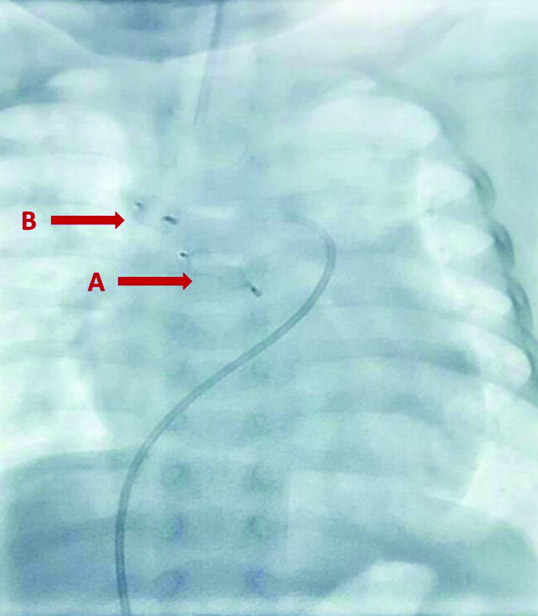

Successful delivery of (A) Proximal vascular plug of 8 mm size and (B) Distal vascular plug of 6 mm size.

Vascular plugs in-situ (A) Proximal vascular plug (post-release), (B) Distal vascular plug (post-release).